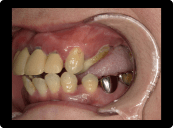

重度歯周炎

中等度の状態がさらに悪化や噛む力や噛み合わせにより進行が加速してしまい、場合によれば抜歯しなくてはいけない状態になるのが重度歯周炎です。

歯を支えている骨の破壊も進行していき、歯が揺れてくる状態になります。歯周ポケットも7〜10mm程度になる場合もあり、通常の歯石取りでは歯石を取り除くことは難しくなります。

歯周外科と言われる歯石除去率を上げるために、歯茎をめくっての歯石取りや再生療法等が必要になる場合もあります。 7〜10mmの深い歯周ポケットは、中等度歯周炎の治療時に行われる縁下歯石取りでも歯石まで器具が届かないや根の形が複雑で40%程度しか取れていないというデータもあります。治療しても揺れが残る場合は、抜歯の検討もしたり、揺れている歯を隣の歯と固定する場合もあります。